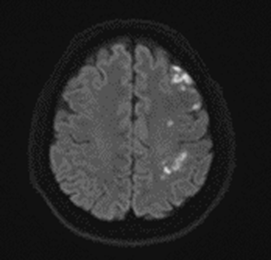

영상 판독 결과, 좌측 중대뇌동맥 영역의 급성 뇌경색이 확인되었어요.

그림4.png 촬영 일시: 2024.08.09

<Fig 1. 뇌경색으로 진단된 뇌 MRI 검사>

다행히 아직 골든타임 내였고,

즉시 혈전용해제(tPA) 투여를 시작했습니다.